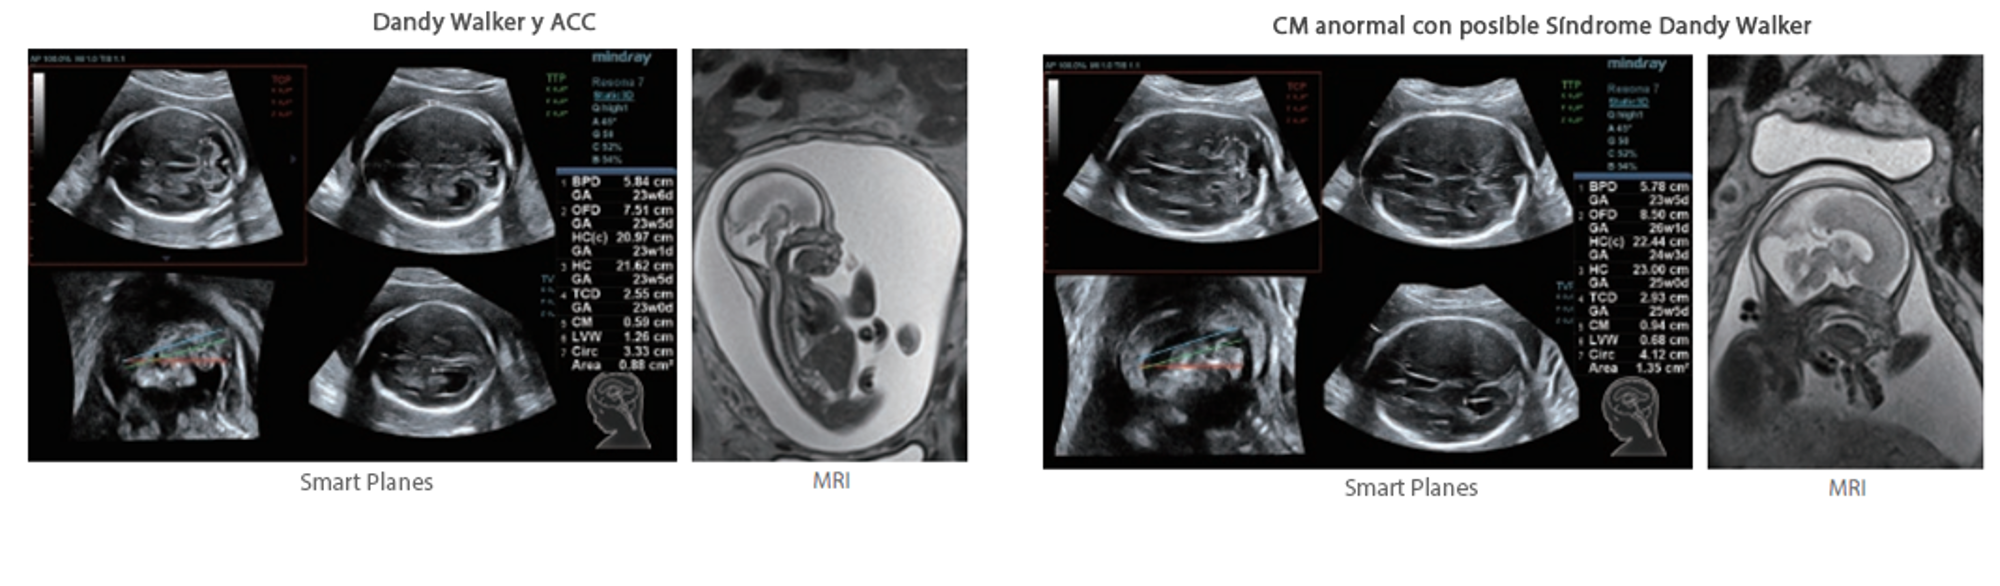

Además de la calidad de imagen de primer nivel, Resona?7 también mejora las capacidades de investigación clínica con el revolucionario V?Flow para la evaluación hemodinámica vascular y con la adquisición de planos más inteligente a partir de conjuntos de datos 3D para el diagnóstico del SNC fetal. Al combinar el funcionamiento multitáctil basado en gestos más intuitivo y todas las características clínicas esenciales, Resona?7 realmente lidera las novedades en innovación de ecografías.